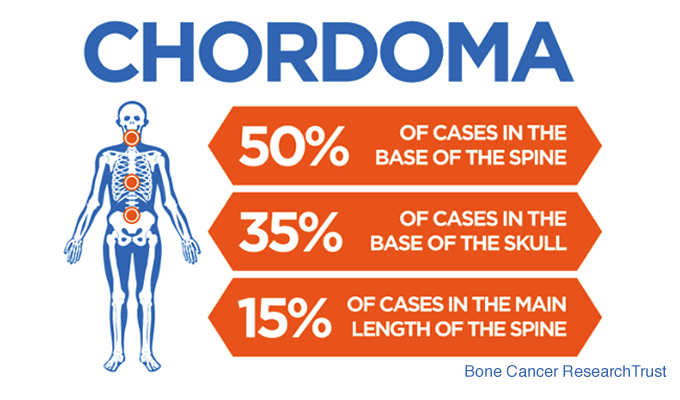

Where Do Chordomas Occur?

Chordomas most commonly arise in three regions:

- The skull base (approximately one-third of cases)

- The mobile spine

- The sacrum